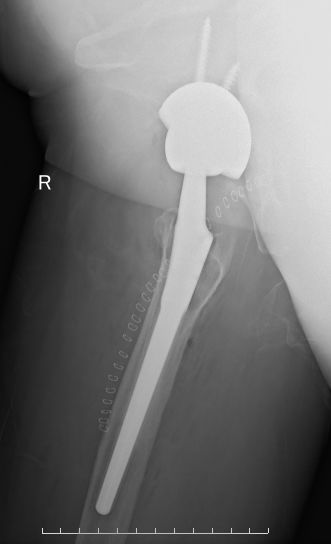

55岁,女性患者,8年前于外院行右侧全髋关节置换术,术后恢复良好;2年前开始出现右髋疼痛,下蹲困难,行走后疼痛明显。门诊以“右髋关节假体松动”收入院。

术前X线片示右侧全髋关节置换术后,假体柄周围见透亮影,考虑假体柄松动